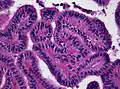

The tumor is neuroectodermal in origin and similar in structure to a normal choroid plexus. They may be created by epithelial cells of the choroid plexus. Papillary fronds lined by bland columnar epithelium are visible under the microscope. Normal absences include mitotic activity, nuclear pleomorphism, and necrosis.[10] Tumors have positive immunohistochemistry for cytokeratin, vimentin, podoplanin, and S-100.[11] Up to 20% of choroid plexus papilloma patients may test positive for glial fibrillary acidic protein (GFAP).[12] Studies have found that fourth ventricle cancers express more S100 than lateral ventricle tumors, and older patients (over 20 years) express more GFAP and transthyretin than younger patients.[13] Some individuals with choroid plexus papilloma have germline TP53 gene mutations, according to genetic analyses.[14] These cancers rarely exhibit nuclear p53 protein positivity. Aicardi syndrome, hypomelanosis of Ito, and 9p duplication are syndromic correlations of choroid plexus papilloma.

Plexuspapillom Detail

Plexuspapillom Detail -